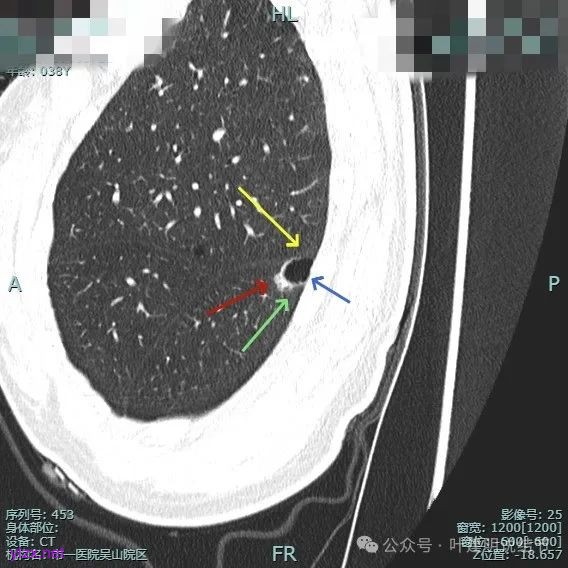

非薄层平扫上这个层面比较明显,似一囊腔,壁厚薄欠均匀。

薄层上看病灶贴着叶间裂与胸膜,此层囊壁薄,囊腔明显。

囊壁局部有增厚。

囊壁局部较厚,但囊壁内也是有小空泡的,病灶贴着胸膜。

病灶部分囊壁是混合磨玻璃成分的,整体轮廓较清。

边缘区也有偏实性成分,磨玻璃成分也还是明显的,有微小血管进入。

靶重建的影像上看,病灶的囊壁明显厚薄不均,有小血管进入,一侧的边似就是斜裂的样子。

囊壁有磨玻璃成分,边缘毛糙,有少许偏实性成分,仍有磨玻璃成分。

血管走向病灶,囊壁略不均。

此层见囊壁有较明显实性成分,血管进入明显。叶间裂侧平直。

混合密度,收缩力不明显,血管进入明显。

囊壁混合密度,整体轮廓清。

表面不平,血管进入,囊壁厚薄不均,紧贴叶间裂。

囊壁里面也有小空泡征。

混合密度但还是太致密,内壁毛糙不平。

病灶轮廓清楚,囊壁厚薄不均,贴着叶间裂与胸膜。

1、诊断问题:这是很典型的囊腔型肺癌,符合我自己之前提出的囊腔型肺癌三要素:(1)囊壁厚薄不均;(2)血管进入囊壁;(3)囊腔内壁不光滑(或再加止整体轮廓与边界较清)。而且由于囊壁实性成分明显,所以是有风险的,要及时干预处理。

2、囊腔型肺癌影像诊断的三要素(叶建明个人总结,仅供参考):囊壁厚薄不均、血管进入囊壁穿行、内壁不光滑(或再加上整体轮廓与边界清楚);